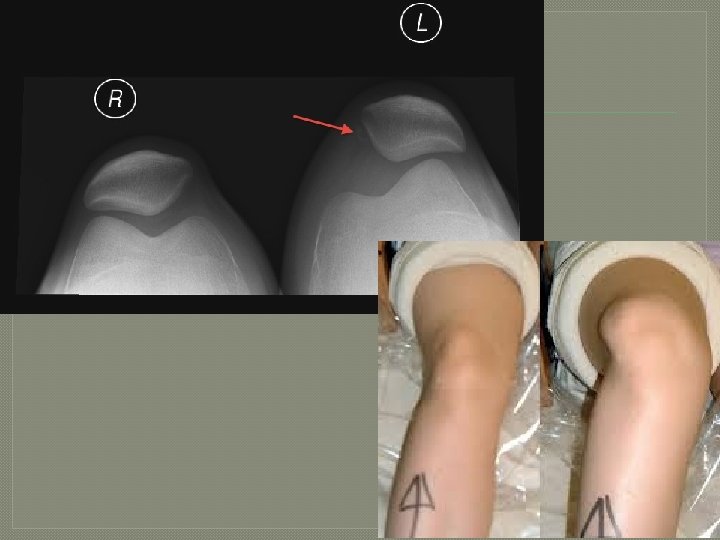

Patellar Subluxation/Dislocation Mechanism of Injury Common Injuries Signs and Symptoms Combination of Obvious deformity, foot planted, pain, swelling, limited deceleration, and ROM. change of direction. Treatment Prevention Strategies RICE and immobilization initially, then ROM and strengthening exercises. Mc. Connell taping or bracing. Lower extremity strengthening and conditioning.